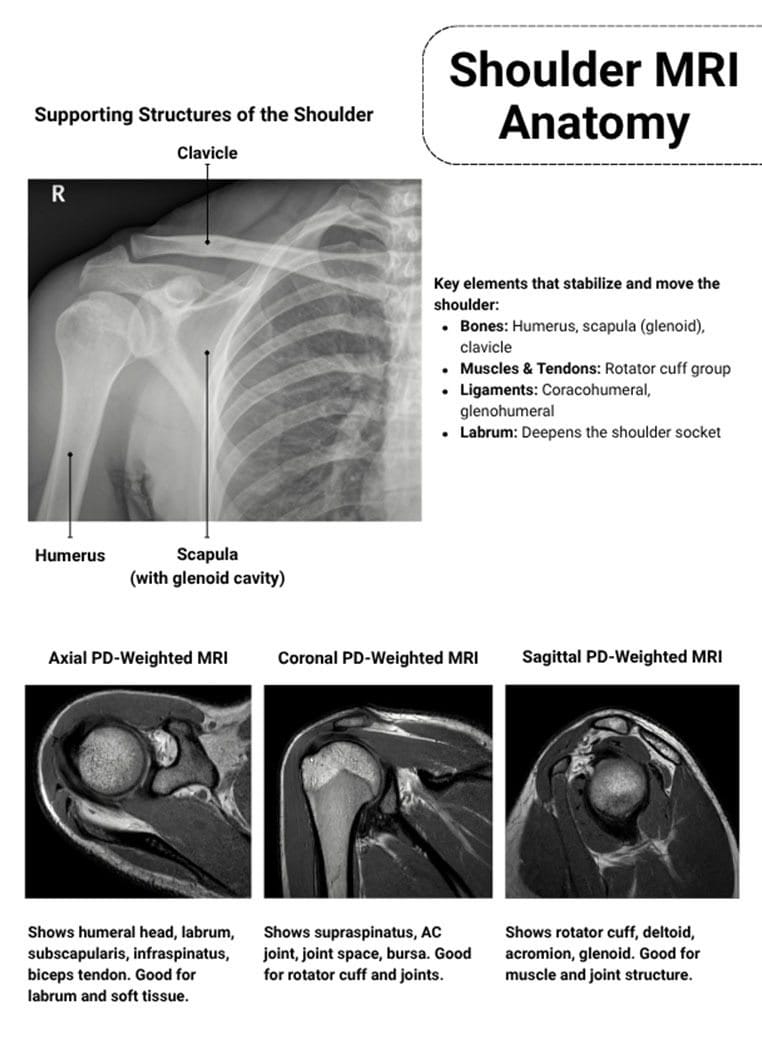

Understanding the Rotator Cuff: What It Actually Does

Before we talk about abnormalities, let's understand what we're actually looking at.

Your rotator cuff isn't one thing. It's a group of four muscles and their tendons that work together to stabilize your shoulder joint. Think of it like a muscular cuff surrounding the ball-and-socket joint of your shoulder, keeping the upper arm bone (humerus) centered in the socket (glenoid).

The four muscles are the supraspinatus, infraspinatus, teres minor, and subscapularis. When they work properly, you can rotate your arm, lift it overhead, and perform thousands of movements without thinking about it. When something goes wrong, you feel it immediately.